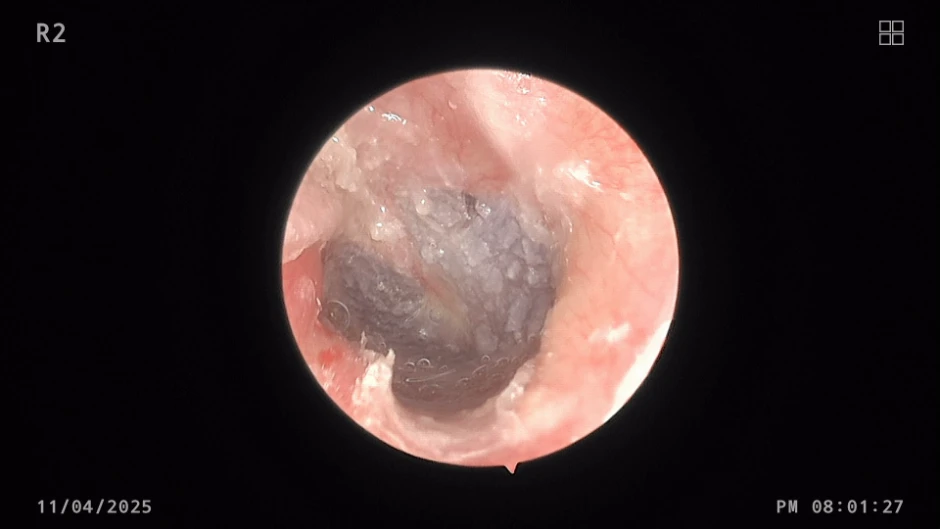

Hậu phẫu ngày thứ 40, da ống tai đã hồi phục hoàn toàn, che phủ toàn bộ ống tai ngoài, màng nhĩ còn nguyên vẹn, bệnh nhân nghe tốt, không ù tai, không đau tai. Ảnh: BVCC

Được biết, ca phẫu thuật lồi xương ống tai ngoài được tiến hành vào cuối tháng 8-2024. Sau phẫu thuật, bệnh nhân được theo dõi sát sao với nhiều đợt kiểm tra định kỳ.

Mặc dù quá trình liền da ống tai kéo dài hơn dự kiến, nhưng với việc sử dụng các biện pháp chăm sóc tại chỗ phù hợp, da ống tai đã hồi phục hoàn toàn, che phủ toàn bộ ống tai ngoài. Đặc biệt, màng nhĩ được bảo tồn nguyên vẹn, chức năng nghe của bệnh nhân trở lại bình thường.

6 tháng sau phẫu thuật: Bệnh nhân nghe tốt, không ù tai, không đau tai, không chít hẹp ống tai. Ảnh: BVCC